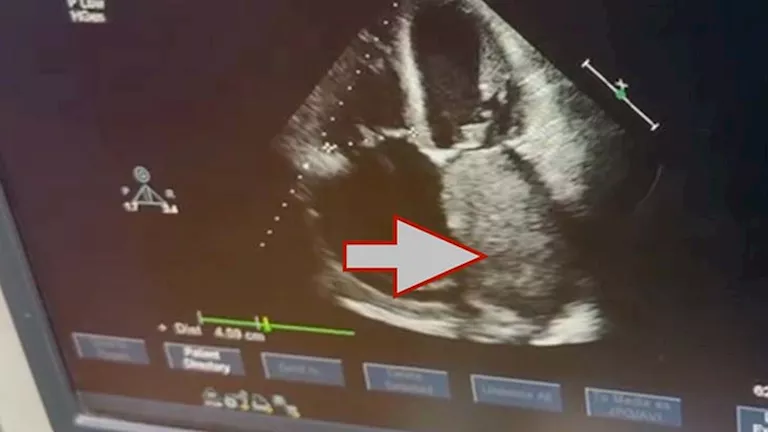

نجح فريق جراحة القلب والصدر بكلية الطب جامعة القاهرة في إجراء جراحة قلب معقدة لاستئصال ورم ضخم من داخل الأذين الأيسر لقلب مريض يبلغ من العمر 72 عامًا، بلغ حجمه نحو 10 × 8 سنتيمترات، وهو حجم نادر لمثل هذه الأورام القلبية.

وأوضح الفريق الطبي أن الورم من نوع Cardiac Myxoma، وهو من الأورام القلبية النادرة التي تنشأ داخل حجرات القلب، وقد تسبب في انسداد شديد بفتحة الصمام الميترالي أثناء تدفق الدم، ما أدى إلى ارتفاع ملحوظ في ضغط الشريان الرئوي، نتج عنه ارتجاع شديد بالصمام الثلاثي الشرفات، إضافة إلى تضخم بالأذين الأيسر وحدوث ذبذبة أذينية.

وكان المريض قد وصل إلى المستشفى وهو يعاني من ضيق شديد في التنفس وكحة دموية خلال الفترة الأخيرة، وهي أعراض ناتجة عن تأثير الورم على حركة الدم داخل القلب.

وخلال الجراحة التي استغرقت نحو أربع ساعات، تمكن الفريق الجراحي من استئصال الورم بالكامل مع قاعدته من الحاجز الأذيني، ثم إعادة ترميم الحاجز الأذيني باستخدام الغشاء التاموري، كما تم إجراء إصلاح جراحي للصمام الثلاثي الشرفات لعلاج الارتجاع الناتج عن ارتفاع ضغط الشريان الرئوي.